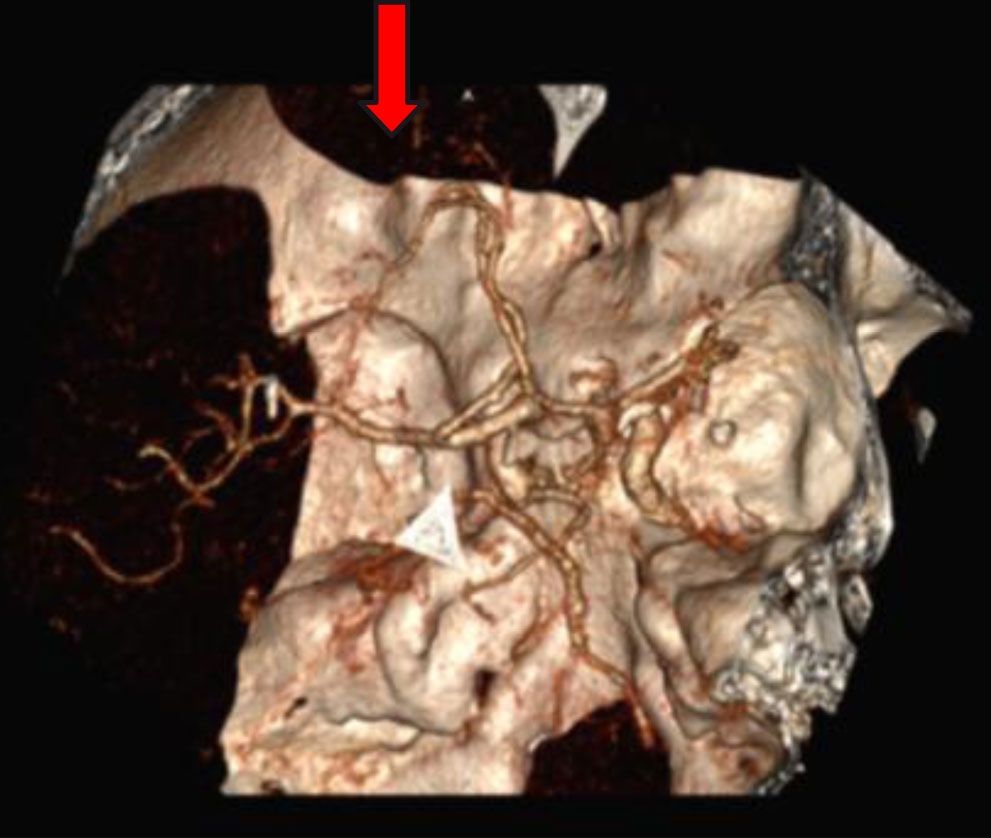

Obr. 1 – Geometrický průměr (n = 6) – Pradaxa 200 mg. aPtt – aktivovaný parciální tromboplastinový čas; ECT – ekarinový koagulační čas; INR – mezinárodní normalizovaný poměr; TT – trombinový čas.Zároveň však bylo jasné, že nejde o selhání léčby jako takové. Bezprostředně provedené tomografické vyšetření (CT) prokazovalo nevýrazné hypodenzity v levé frontální oblasti parasagitálně a okluzi periferie levé arteria cerebri anterior (ACA) (obr. 2).

Obr. 2 – CTAG s průkazem okluze periferie ACA vlevo• Časová osa: